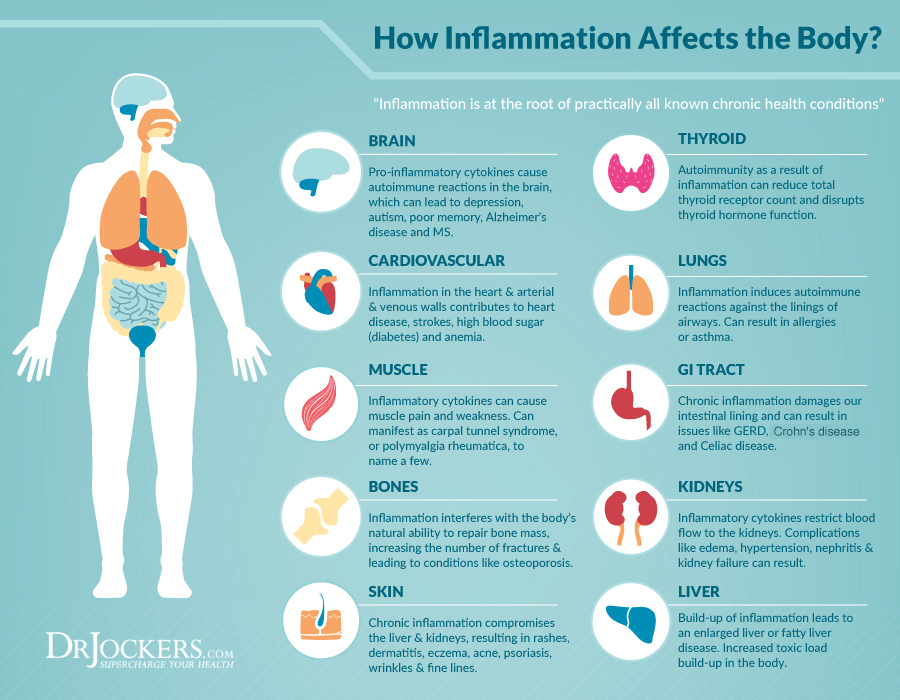

We have a natural remedy for youHow does inflammation affect the body?

#1: Brain

Anti-inflammatory cytokines cause autoimmune reactions in the brain that can lead to depression, autism, poor memory, Alzheimer's disease and MS.

#2: Thyroids

Autoimmunity can reduce the total number of thyroid receptors and interfere with thyroid hormone function as a result of inflammation.

#3: Cardiovascular system

Inflammation of the walls of the heart, arteries and veins causes heart disease, stroke, high blood sugar (diabetes) and anaemia.

#4: Lungs

Inflammation triggers autoimmune reactions against the lining of the airways. Can cause allergies or asthma.

#5: Muscles

Inflammatory cytokines can cause muscle pain and weakness. This can take the form of, for example, carpal tunnel syndrome or polymyalgia rheumatica.

#6: Digestive tract

Chronic inflammation damages the lining of our gut and can lead to problems such as reflux, Crohn's disease and coeliac disease.

#7: Bones

Inflammation interferes with the body's natural ability to repair bone mass, increasing the number of fractures and causing diseases such as osteoporosis.

#8: Kidneys

Inflammatory cytokines restrict blood flow to the kidneys. Complications such as swelling, hypertension, nephritis and kidney failure can result.

#9: Skin

Chronic inflammation threatens the liver and kidneys, resulting in rashes, skin inflammation, eczema, acne, psoriasis, wrinkles and fine lines.

#10: Liver

The accumulation of inflammation leads to enlarged liver or fatty liver disease. Increased accumulation of toxic load in the body.